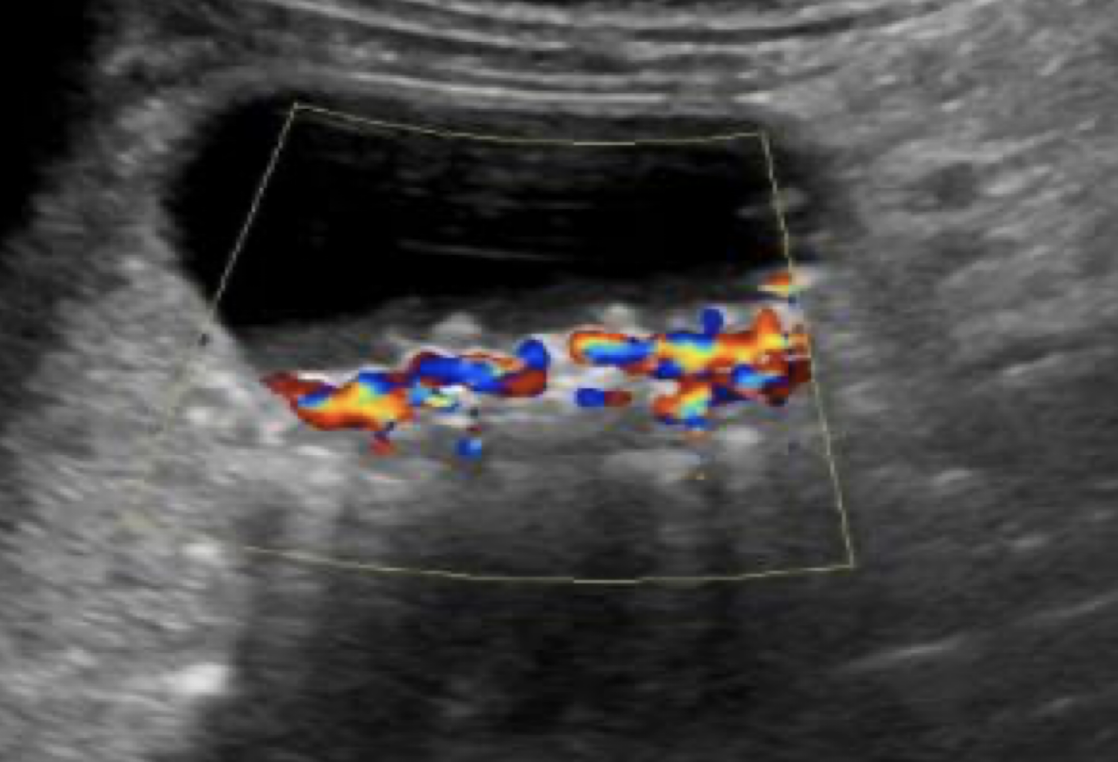

SONO: cholelithiasis

twinkle artifact

twinkle artifact from stones

??

twinkle artifact from stone